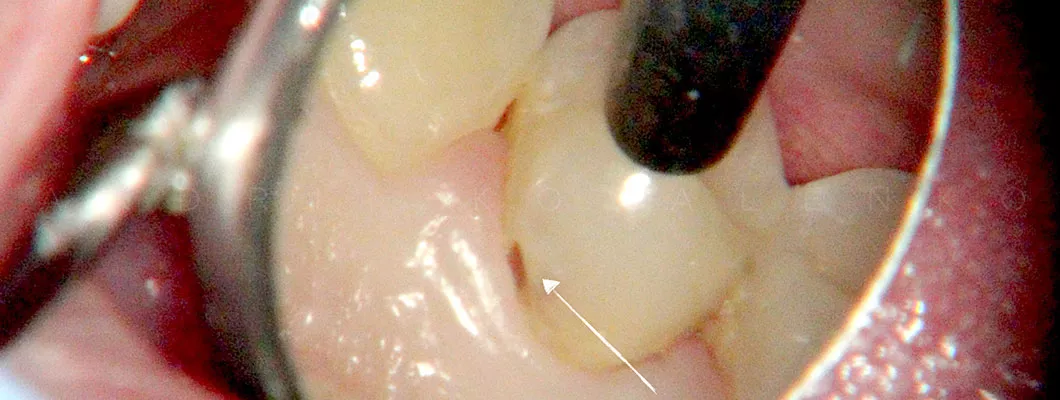

Завдяки ефективному використанню дентального мікроскопа, ми можемо виявити каріозні враження зубів на ранніх стадіях, які є недоступними для неозброєного ока.

Фото жувального зуба враженого карієсом

Однією з найвагоміших переваг до виконання реставрацій з використанням мікроскопа в Olanko dental studio (Оланко) м. Бровари, є можливість дбайливого поводження з зубними тканинами.

Лікар, працюючи під збільшенням, зішліфовує тільки вражені карієсом тканини, тим самим максимально зберігає об`єм зуба.